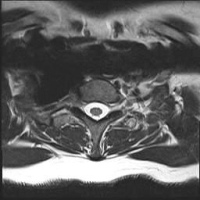

Using very small tools, the spurs are removed and the herniations are removed. A graft is then used to be placed in between the vertebral bodies to cause them to fuse together. The graft can be from your own bone (ICBG-iliac crest bone graft) or a PEEK cage which acts as a spacer and is filled with your own bone and demineralized bone matrix (DBM). The PEEK cage is imbedded with a thin film of titanium (see image) which is biologically active and allows bone to adhere to it. The discussion as to which graft to be used will be made before the anterior cervical decompression and fusion (ACDF) surgery is scheduled. Both grafts have advantages and disadvantages that will be discussed.

PEEK Cage